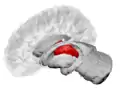

Thalamus

The thalamus (from Greek θάλαμος, "chamber")[1] is a large mass of gray matter located in the dorsal part of the diencephalon (a division of the forebrain). Nerve fibers project out of the thalamus to the cerebral cortex in all directions, allowing hub-like exchanges of information. It has several functions, such as the relaying of sensory signals, including motor signals to the cerebral cortex[2][3] and the regulation of consciousness, sleep, and alertness.[4]

![]() The thalamus in a 360° rotation | |